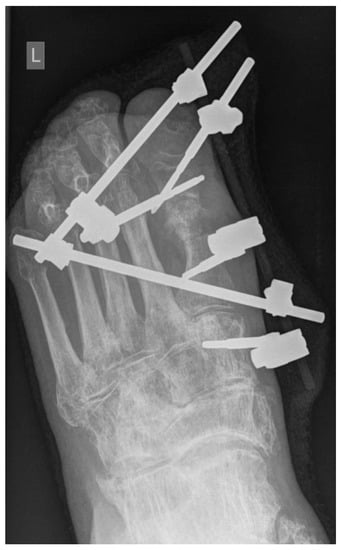

2.3. Surgical Technique